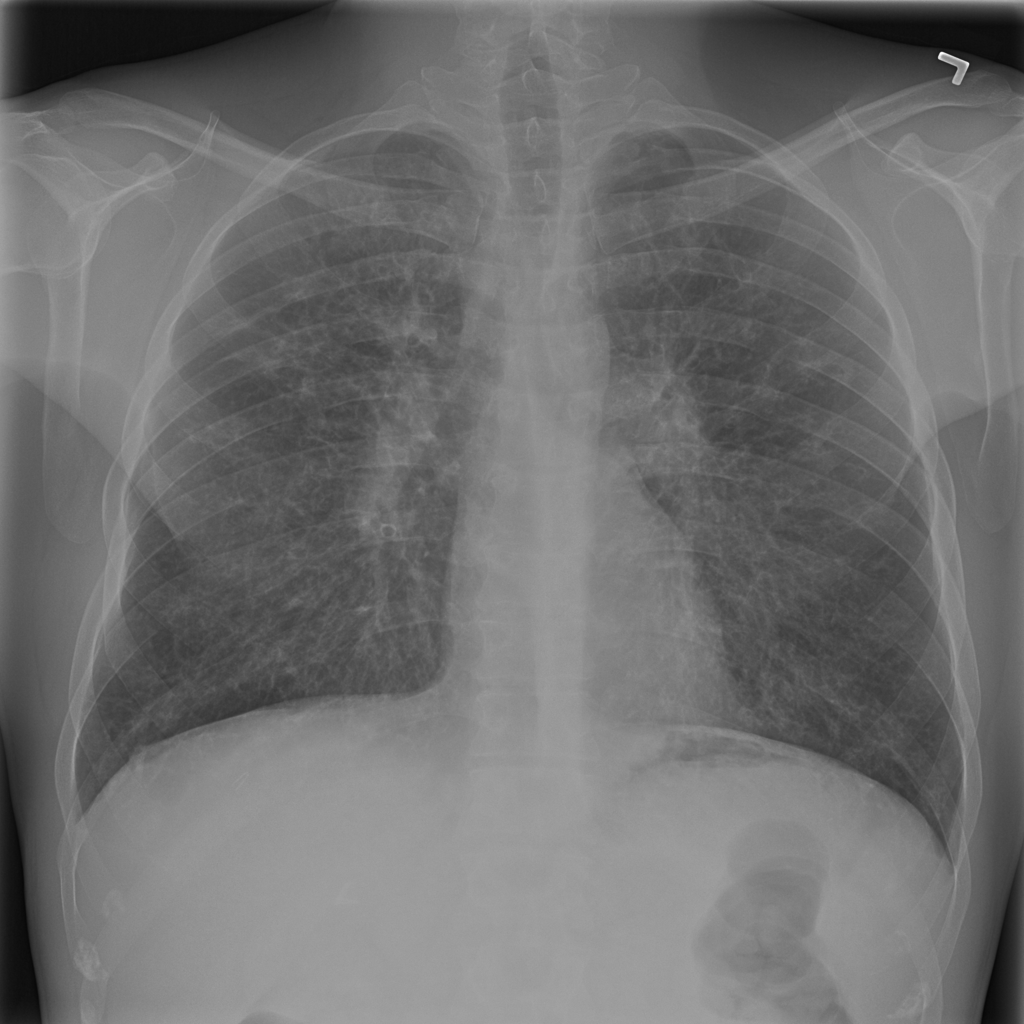

Showing up to 90 reference images for Fibrosis.

PAT-E960 · IMG-002Fibrosis

PAT-E960 · IMG-002

PA